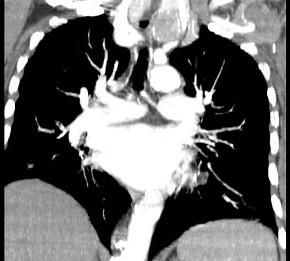

问题 40岁,女,发现颈部肿块,随吞咽上下移动,触之无搏动,咳嗽、气喘一周,请结合CT图。检查选择最可能的诊断 ( )

选项 A、无名动脉伸展扭曲 B、淋巴瘤 C、胸内甲状腺瘤 D、无名动脉瘤 E、胸腺瘤

答案 C